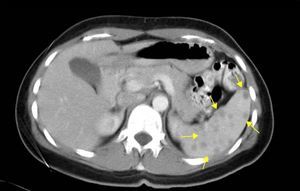

Mujer de 37 años de raza caucásica, sin antecedentes médicos de interés. Presentaba desde hacía años dolor en el epigastrio y el hipocondrio izquierdo punzante leve e intermitente diario, sin relación con la ingesta ni alteración del tránsito digestivo, con ausencia de otra sintomatología sistémica asociada. La exploración física era normal. Su estudio analítico mostró reactantes de fase aguda, frotis de sangre periférica, proteinograma y niveles de enzima convertidora de angiotensina normales; además de pruebas de autoinmunidad, serología infecciosa (incluyendo hidatidosis) y prueba de Mantoux negativos. Las radiografías de tórax y abdomen, el tránsito gastrointestinal y el electrocardiograma fueron normales. La ecografía abdominal y la tomografía computarizada toracoabdominal mostraron múltiples lesiones esplénicas de 7-9mm de diámetro sin esplenomegalia (fig. 1). La resonancia magnética abdominal mostró múltiples lesiones en el bazo, hipointensas en T2 e isointensas en T1, con realce homogéneo y tardío de contraste, con diámetro menor a 1cm (fig. 2). Ante la persistencia del dolor en hipocondrio izquierdo, así como incertidumbre diagnóstica, se decidió realizar esplenectomía laparoscópica. Macroscópicamente, el bazo presentaba múltiples nódulos externos e intraparenquimatosos de aspecto blanco-fibroso y con diámetro inferior a 1cm; negativos a pruebas microbiológicas, histológicamente compatibles con granulomas epitelioides no caseificantes (fig. 3). Tras la esplenectomía sin complicaciones, la paciente permaneció asintomática y sin tratamiento alguno en el seguimiento actual.